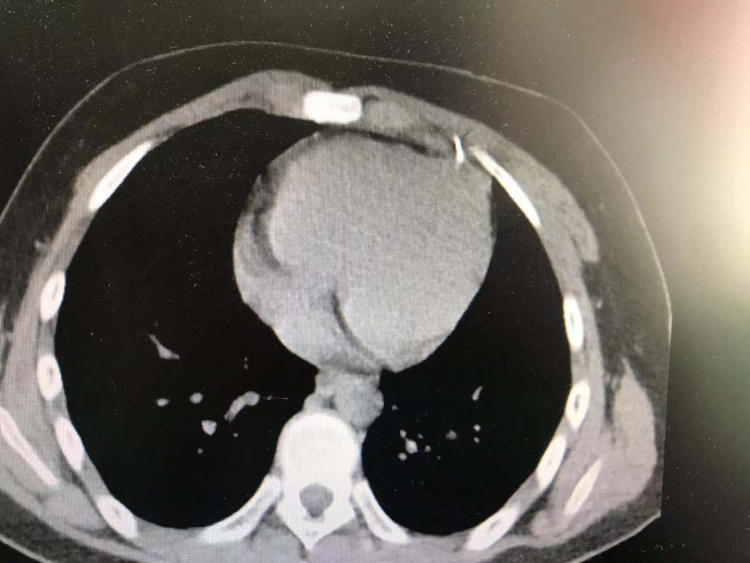

CT检查提示断针位置非常凶险,部分已经进入心脏,必须立即手术。

史常文告诉记者,针的位置部分已经进入心脏,最怕就是可能出现的严重的室性心律失常和心包填塞,如果出现可能危及患者生命。好在取异物技术在医院已很成熟,在定位仪的帮助下,顺利取出异物。经过测量,针长达4厘米。